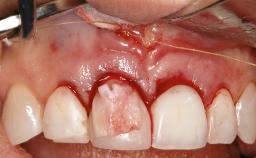

Peri-Implant Mucositis Treatment Outcomes on an Implant with a Submucosal Restoration Margin

Mauricio Araujo and Flauvia Matarazzo present this straightforward clinical case, demonstrating the potential effect of implant placement depth on the resolution of peri-implant treatment. A 42-year-old systemically healthy female patient, a non-smoker with no history of periodontitis, was treated at the Dental Clinic at the State University of Maringá, Brazil between 2008 and 2009, when she received five implants restored with single crowns at sites 14, 26, 27, 36, and 46. After delivery of the implant-supported prosthetic restorations, the patient was enrolled in the supportive peri-implant therapy (SPiT) maintenance program at the same university.